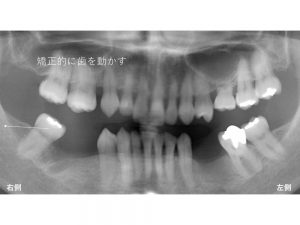

まず初診のレントゲンから見てみましょう。

下顎左右の奥歯が欠損しています。

右側の奥歯は2歯が欠損しています。

ここで問題となるのが下顎右側の一番奥歯です。

一番奥歯が斜めに傾斜しているのです。

そこで下顎右側の一番奥歯を矯正的に移動させることが必要です。

以下のようにです。